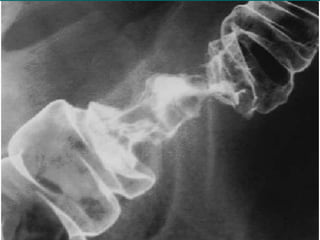

ETAPIFICACION Dukes mod. Astler-Coller

A Lesión que no penetra la mucosa.

B1 Lesión hasta serosa pero sin penetrarla.

B2 Lesión que penetra serosa afectando

órganos adyacentes.

C1 Lesión hasta serosa pero sin penetrarla,

con metástasis ganglionares.

C2 Lesión que penetra serosa, afectando

órganos adyacentes y metástasis

ganglionares.

D Enfermedad metastasica a distancia.

CANCER DE COLONY RECTO ETAPIFICACION Dukes mod. Astler-Coller A Lesión que no penetra la mucosa. B1 Lesión hasta serosa pero sin penetrarla. B2 Lesión que penetra serosa afectando órganos adyacentes. C1 Lesión hasta serosa pero sin penetrarla, con metástasis ganglionares. C2 Lesión que penetra serosa, afectando órganos adyacentes y metástasis ganglionares. D Enfermedad metastasica a distancia.